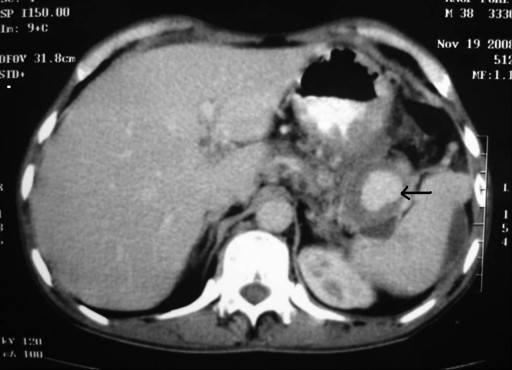

A 46-year-old male with a history of chronic alcoholism having a 3-week history of alcohol-related severe acute pancreatitis was referred to our institution for a necrosectomy. He was initially treated at a district hospital and was referred to us owing to persistent high fever not responding to antibiotics. After admission injection meropenem and fluconazole were initiated. He responded initially but fever recurred on the 7th day after admission. After exclusion of other sources of infection, a contrast-enhanced computed tomography (CECT) of the abdomen was carried out which showed more than 50% necrosis of the pancreas with a large pseudoaneurysm of the splenic artery (Figure 1). As a result of this, the patient was scheduled for a necrosectomy and ligation of the pseudoaneurysm the following day. Unfortunately, the patient hemorrhaged that night. An upper gastrointestinal endoscopy was performed and bleeding from the papilla was detected. As the CECT showed a pseudoaneurysm of the splenic artery, a ruptured pseudoaneurysm was diagnosed as the source of the bleeding. Emergency surgery was performed immediately. A necrosectomy was performed with multiple drains placed for continuous lavage, ligation of the pseudoaneurysm from the necrosectomy cavity and a feeding jejunostomy. Intraoperative blood loss was 1.5 liters. The patient needed postoperative mechanical ventilation. Although the postoperative course was difficult, the patient recovered slowly over a period of 34 days and was well at a 26-month follow-up.

Figure 1. CECT abdomen showing a large pseudoaneurysm of the splenic artery (black arrow) (Case #1). |